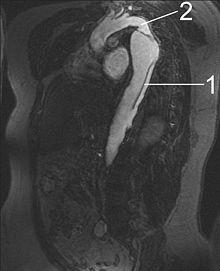

MRI of an aortic dissection

1 Aorta descendens with dissection

2 Aorta isthmus

Magnetic resonance imaging (MRI) is also used for the detection and assessment of aortic dissection, with a sensitivity of 98% and a specificity of 98%. An MRI examination of the aorta produces a three-dimensional reconstruction of the aorta, allowing the physician to determine the location of the intimal tear and the involvement of branch vessels, and to locate any secondary tears. It is a noninvasive test, does not require the use of iodinated contrast material, and can detect and quantitate the degree of aortic insufficiency.

The disadvantage of the MRI scan in the face of aortic dissection is that it may be available only in larger hospitals, and the scan is relatively time-consuming, which could be dangerous in people who are already very unwell. Due to the high-intensity magnetic fields used during MRI, it cannot be used on individuals with metallic implants. In addition, some individuals experience claustrophobia while surrounded by the MRI magnet.